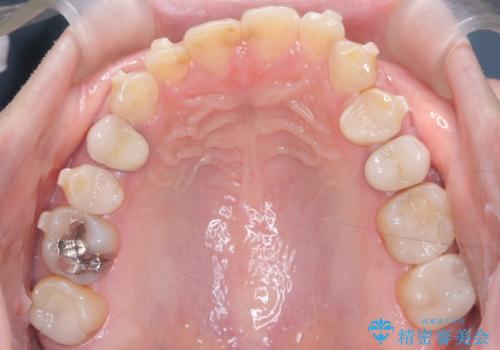

- 下の前歯のデコボコ(叢生)を気にされてご来院されました。精密な検査の結果、下の前歯を並べるスペースが不足していることが判明。患者様のご希望から、透明で目立ちにくい**インビザライン(マウスピース矯正)による治療計画を立案しました。主に歯の側面をわずかに削るIPR(歯間乳頭保護下ストリッピング)**などでスペースを確保し、下の前歯の叢生を解消することを目指します。

今回の矯正治療では、透明なマウスピース型の装置インビザラインを使用しました。目立たず、取り外しが可能なため、日常生活にほとんど影響なく治療を進めることができました。治療は、緻密に計算された計画に基づき、IPRなどで必要なスペースを確保しながら、下の前歯をスムーズに移動。これにより、長年の悩みであった下の前歯のデコボコが解消され、清掃しやすい、整った歯並びを獲得していただけました。